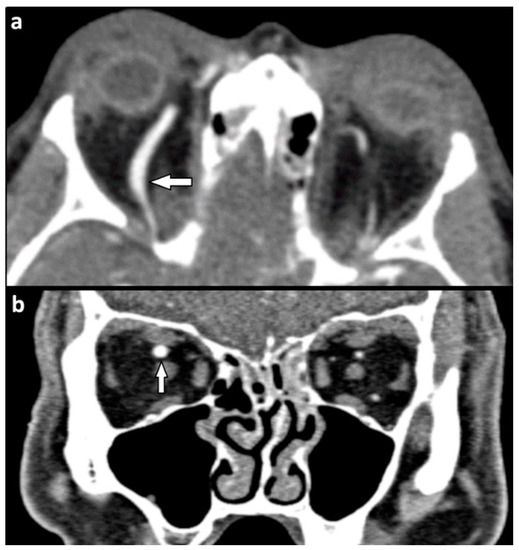

| Orbital vessels | 16 (15.8) | |

| dilated superior ophthalmic vein | 10 (9.9) | |

| direct carotid cavernous fistula | 6 (5.9) |